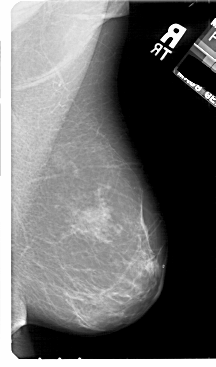

A_1811_1.LEFT_MLO

LEFT_MLO LINES 5491 PIXELS_PER_LINE 3301 BITS_PER_PIXEL 12 RESOLUTION 43.5 OVERLAY